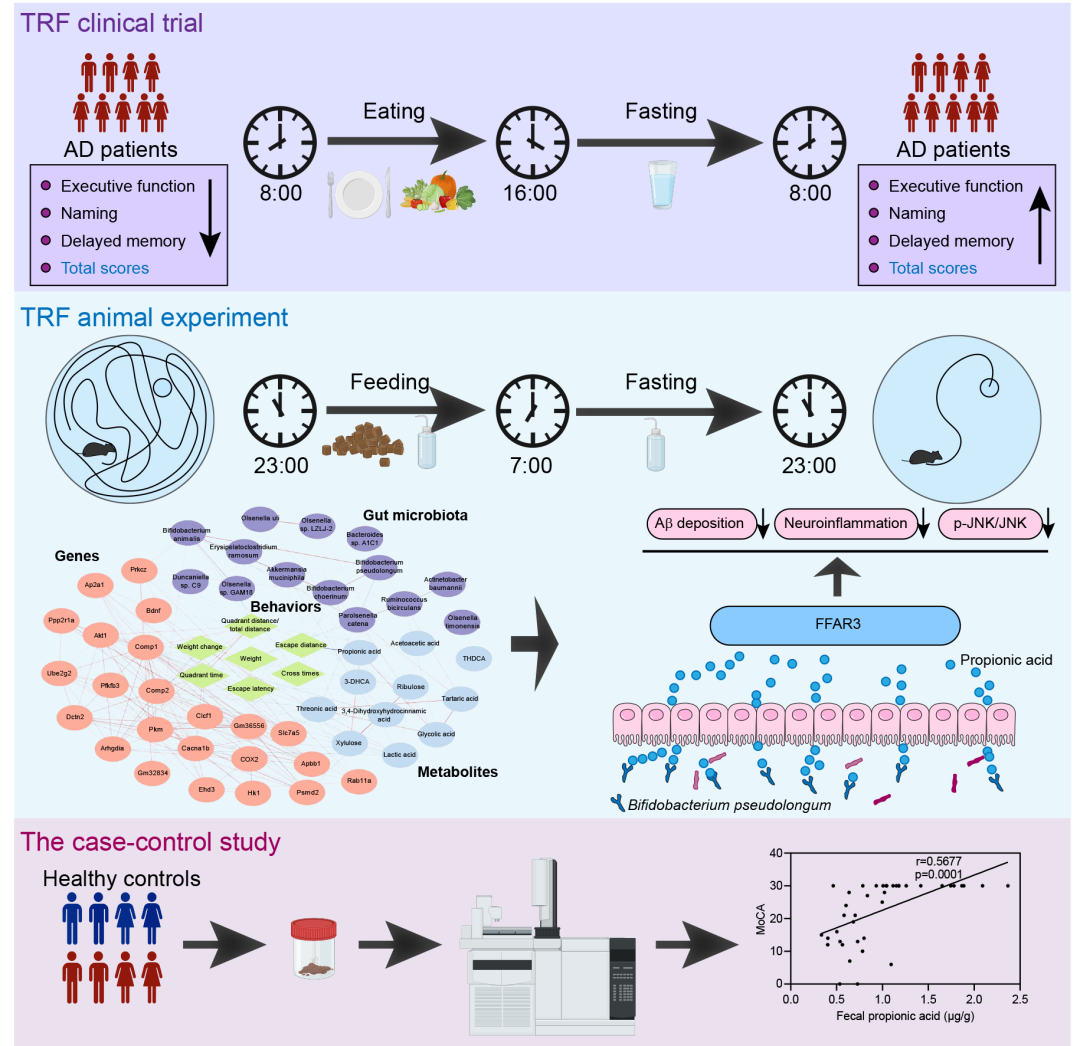

在本研究中,我们首先进行了一项为期4个月的小规模TRF临床干预试验,以评估其对AD患者(n = 9)认知功能的影响(图1A)。认知功能测试表明,TRF显著提高了AD患者的蒙特利尔认知评估(MoCA)分数,特别是在执行功能领域(p < 0.05),强调了TRF干预对AD患者认知障碍的缓解作用(图1B)。

为研究TRF对AD引起的认知障碍和病理损伤的保护作用的潜在生物学机制,我们使用6月龄的5xFAD小鼠进行实验,让其自由进食或每天进食8小时,持续3个月(图1C)。Morris水迷宫测试显示,与野生型(WT)小鼠相比,AD小鼠在5天的初始空间训练期间的逃避潜伏期时间显著延长,而TRF干预可逆转这一现象(图1D)。此外,TRF显著提高了AD小鼠在目标象限的停留时间(图1E)和在目标象限中路程比(图S1F),恢复至WT小鼠的正常水平,表明TRF可改善AD小鼠空间记忆能力。免疫荧光染色结果进一步证实,AD小鼠皮层和海马中Aβ和离子化钙结合衔接分子1(Iba-1)大量聚集,表明AD诱导了显著的淀粉样蛋白沉积和小胶质细胞活化(图1F和图S1H)。TRF干预显著减少了AD小鼠脑内Aβ斑块的阳性面积,并增加了小胶质细胞的聚集(图1G、H和图S1I、J),同时降低了促炎细胞因子肿瘤坏死因子-α(TNF-α)和白细胞介素-1β(IL-1β)的mRNA表达水平(图1I、J)。此外,TRF干预显著增加了AD小鼠皮层中脑源性神经营养因子(BDNF)的mRNA表达(图S1K),这一基因对神经元的存活、维持及再生至关重要。我们的研究结果共同表明,TRF增强了AD患者和AD小鼠的认知记忆功能,并通过促进Aβ斑块周围小胶质细胞的聚集,同时减少Aβ沉积和神经炎症,显著缓解AD的病理表现。

图1. 限制时间饮食(TRF)缓解AD相关的认知损伤

(A)AD患者接受为期4个月的TRF干预的示意图(n = 9);(B)TRF干预前后AD患者蒙特利尔认知评估(MoCA)总分及各子项目(执行功能、命名、注意力、语言、抽象功能、延迟记忆、定向能力)的量化分析;(C)每组接受TRF或自由进食(ad libitum)干预的实验流程示意图(n = 6-10);(D)逃避潜伏期;(E)目标象限的停留时间;(F)小鼠皮层中淀粉样β(Aβ)沉积(绿色)及离子化钙结合适配分子1(Iba-1+)阳性小胶质细胞(红色)的免疫荧光染色图像(n = 3)(比例尺:100 μm);(G)Aβ斑块阳性区域的定量分析;(H)Aβ斑块相关小胶质细胞的定量分析;(I)肿瘤坏死因子-α(TNF-α)的mRNA水平测定(n = 6);(J)白细胞介素-1β(IL-1β)的mRNA水平测定(n = 6)。数据以均值 ± SEM表示。*p < 0.05,**p < 0.01;双因素方差分析(two-way ANOVA)结合Tukey多重比较检验。

先前的研究表明,维持TRF干预6个月可改善老年人的认知状态。虽然统计能力受到样本量的限制,但我们的结果证明4个月的TRF增强了AD患者的认知能力(图1)。最近的研究表明,TRF通过上调BDNF水平、降低炎症因子(IL-6和TNF-α)的表达和促进神经发生发挥神经保护作用。研究表明,间歇性禁食和卡路里限制对AD样病理有抑制作用,表现为降低脂蛋白脂肪酶表达、降低Aβ40和Aβ42水平、降低磷酸化tau水平。最新研究从昼夜节律的角度解释了TRF对AD认知和Aβ沉积的改善作用,重点强调TRF干预通过恢复脑转录过程的紊乱,从而改善AD引起的睡眠障碍。尽管TRF对认知障碍和神经损伤的作用机制和影响尚有争议,但本研究证实TRF增强了AD小鼠的空间记忆能力、减少了Aβ的沉积、促进了小胶质细胞向斑块的聚集、提高了BDNF水平(图1)。海马转录组的PLSDA有效地区分了AD+TRF组和AD组之间的基因贡献者,包括Cacna1b、Prkcz和COX2。TRF显著增加Cacna1b和Prkcz表达,同时降低COX2表达(图S2)。据报道,Cacna1b参与维持突触信号传导,其失调与AD的发病机制有关。由Prkcz编码的蛋白激酶C的激活可调节BACE1的活性并控制Aβ前体APP的裂解。此外,COX2被发现介导IL-1β和Aβ之间的相互调节,促进AD的发病机制。这些发现表明TRF对神经退行性疾病的发展具有有益作用。具体而言,TRF诱导的差异表达基因可作为治疗AD的潜在靶点。